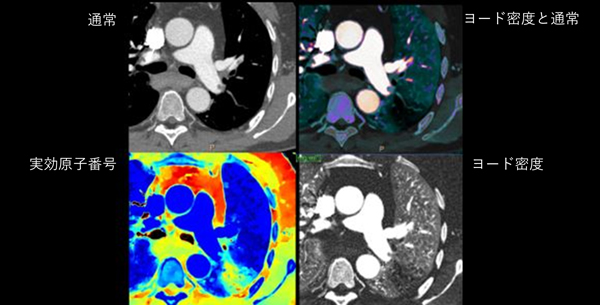

スペクトラルCTは普通のCTと異なります。

本来X線の波長は連続スペクトルを持つため、低いエネルギーから高いエネルギーまで多くの情報を持っています。しかし通常のCTは単一エネルギーしか使用することができないため、それぞれのエネルギーの特徴を活かすことができず、白黒の画像しか得ることができませんでした。

一方、スペクトラルCTはX線を検出する側である「検出器」の構造が特殊です。この検出器が2層あることでX線が持つ各エネルギーの情報を分別して取得することができ、これによって普通のCTではできなかった以下の画像を取得することが可能となりました。

- 実効原子番号画像

物質の実効原子番号を画像化し、定量値という値によって物質を推定することができます。尿路系や胆管内の結石の成分解析や肺の還流領域の描出などが可能です。 - カルシウム抑制画像

物質の電子密度の値を画像化することができるため、転移性肝腫瘍などの存在や心臓の心筋の質的診断などの一助となります。 - ヨード密度画像

ヨード(造影剤)密度量を反映した画像です。従来画像に重ねあわせることで、カラー表示で閲覧することも可能です。ヨード量を計測することで、定量的に造影剤の取り込みを評価することができます。 - 仮想非造影画像